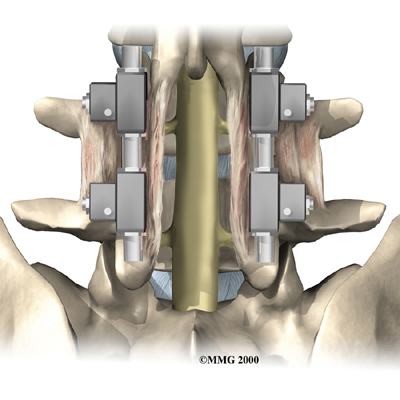

Posterior Fusion with Instrumentation

A spinal fusion is normally done immediately after laminectomy for spondylolisthesis. The fusion procedure is designed to fuse the two vertebrae into one bone and stop the slippage from worsening. The fusion is used to lock the vertebrae in place and stop movement between the vertebrae, easing mechanical pain. When combined with laminectomy surgery (mentioned earlier), fusion helps relieve nerve compression.

In this procedure, the surgeon lays small grafts of bone over the back of the problem vertebrae. Sometimes fusion is done just with bone graft material. This is a fusion without fixation (non-instrumentation). Instrumentation is the use of metal plates or screws to stabilize the segment during healing. Most surgeons combine fusion with instrumentation to prevent the two vertebrae from moving. This protects the graft so it can heal better and faster.

Outcomes are improved when decompression is combined with fusion (compared with decompression alone). Fusion and functional improvement are even better when spinal instrumentation is used. There are fewer long-term problems with pain and pseudoarthrosis (formation of movement or false joints within the fusion).

Related Document: Iron City Physical Therapy's to Posterior Lumbar Fusion